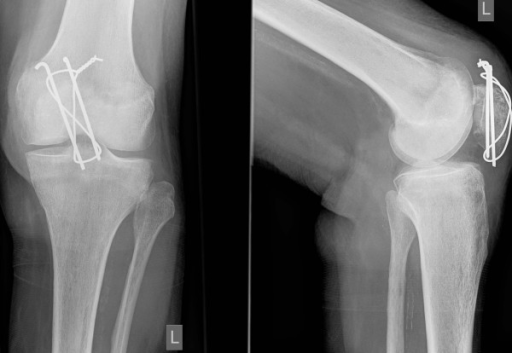

Lo más increíble, además de haber sobrevivido, es que no recuerda nada de lo que ocurrió desde el sábado anterior al accidente y hasta dos meses luego de la caída. Cuando despertó del coma inducido, se percató que estaba en una cama de hospital rodeado de placas de hierro para apoyar su débil estructura ósea.

Pablo sufrió alrededor de 124 fracturas, sin embargo, después de casi 12 meses de tratamiento se recuperó exitosamente.

“Tenía casi todos los huesos quebrados” pero sin daños cerebrales y con la columna vertebral a salvo, comentó en ese instante el doctor Sergio Sánchez, director general del Hospital de Urgencia y Asistencia Pública, también conocido como Posta Central de Santiago.